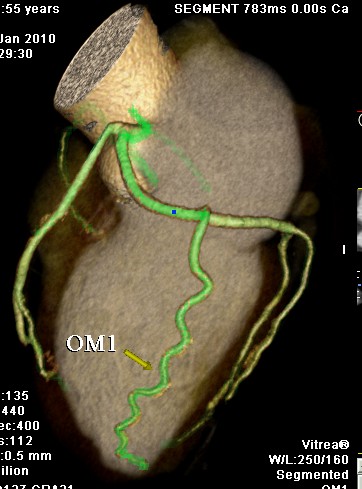

标题: CT24400:患者54岁,心前区不适进行心脏冠脉造影检查。 [打印本页]

标题: CT24400:患者54岁,心前区不适进行心脏冠脉造影检查。

患者54岁,心前区不适进行心脏冠脉造影检查。高手看看有问题没有?

图像很漂亮,好像未见异常